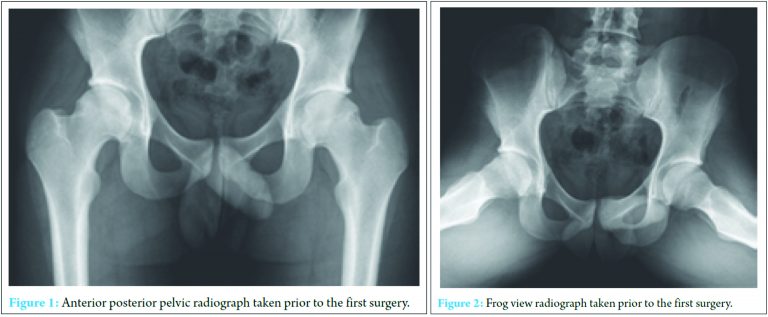

Informed consent was obtained from the patient for the use of all images and publication of this report before the beginning of this project. A 20-year-old basketball player presented with a 2-year duration of the left groin pain after a basketball-related injury. The pain was aggravated by athletic activity and prolonged sitting. Physical examination of the left hip showed pain with hip external rotation at 40° and internal rotation at 10°. Radiographs showed a lateral center-edge angle of 36° and an alpha angle of 83° on the anterior–posterior (AP) and 72° on the frog view (Fig. 1 and 2). Due to continued disability and failure of conservative management, the patient underwent hip arthroscopy.